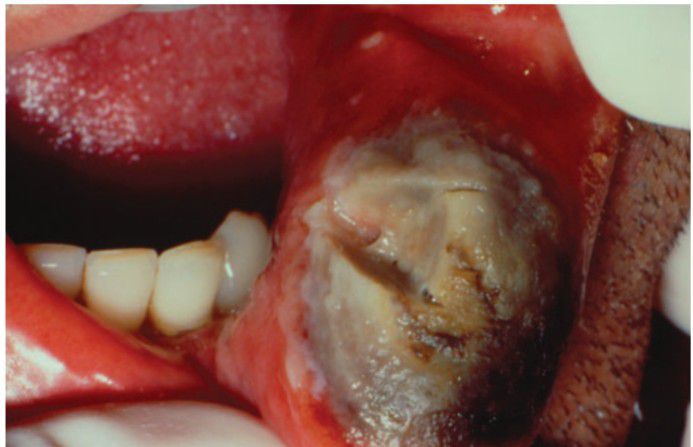

Tissue necrosis

Extensive tissue necrosis caused by injudicious use of silver nitrate.